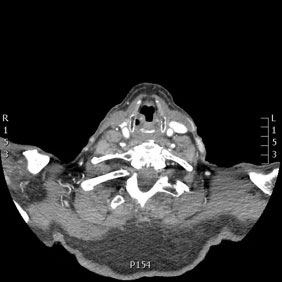

Tomografía computarizada Cuello

< Volver a "Tomografía Computarizada (TC) con Inteligencia artificial"Está indicado para el estudio de las diferentes patologías y estructuras del cuello (arterias, venas, ganglios, glándulas,…).